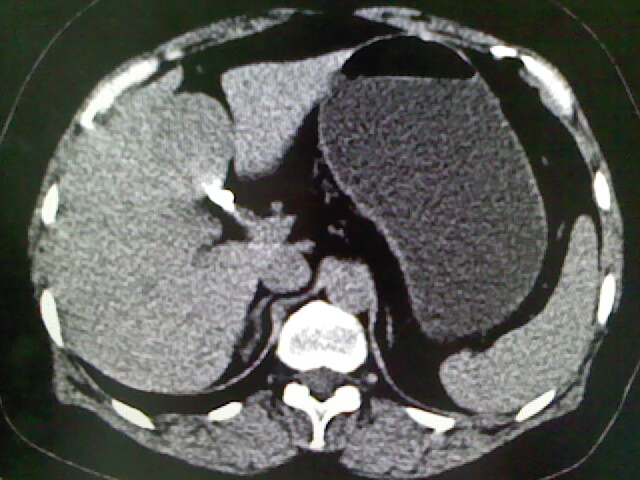

以下是引用卜一在2009-4-2 13:26:00的发言:[br]胆囊颈部结石伴胆囊炎!另:建议增强,待除外肝内占位及胆囊占位!

以下是引用liaoqiang在2009-4-2 16:23:00的发言:[br]胆囊是否切除?胆囊颈区致密影考虑金属夹?结石?肝脏右叶低密度影,考虑增强。